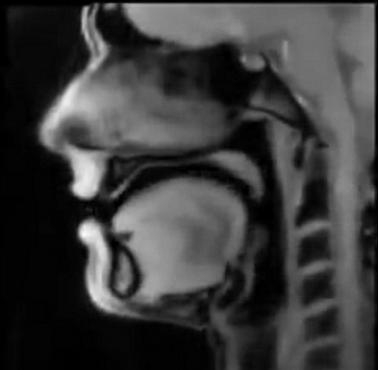

Tętnice szyjne na skanie rezonansu magnetycznego (MRI)